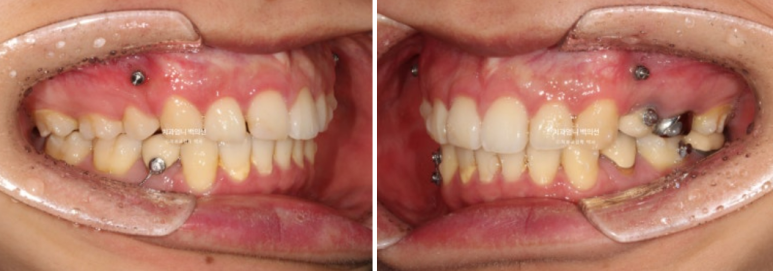

2024년 6월부터 11월까지, 20개의 추가장치를 모두 낀 후 모습입니다.

24.11

앞니 사이 틈은 없어졌고 중심선은 정확히 맞습니다.

교합도 퍼펙트 합니다.

입안 사진만 보면 치료를 마무리해도 됩니다.

그런데

얼굴 전체로 봤을 때 앞니 기울어짐이 눈에 띕니다.

입안 사진으론 알 수 없어요. 얼굴사진을 중간중간 찍어서 확인해야 하는 부분입니다.

환자분은 딱히 인지하지 못했지만 더 좋은결과를 위해 두번째 재제작에 들어갑니다.